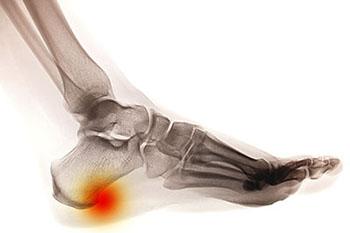

Heel spurs are brought upon by a calcium deposit that causes a bony protrusion on the underside of the heel bone. It normally forms over time and can best be diagnosed through an x-ray examination. Heel spurs are commonly linked with plantar fasciitis, an inflammation that runs along the bottom of the foot. Common symptoms of heel spurs include pain towards the affected area, inflammation, and swelling at the front of the heel.

Heel spurs are calcium deposits that produce bony growths on the underside of the heel bone. They may or may not cause heel pain. Heel spurs are typically diagnosed through an X-ray.